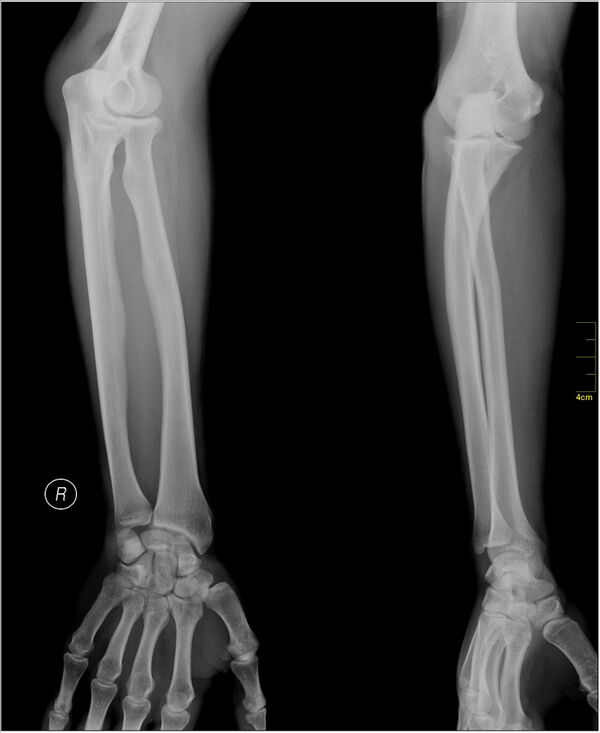

Изображения